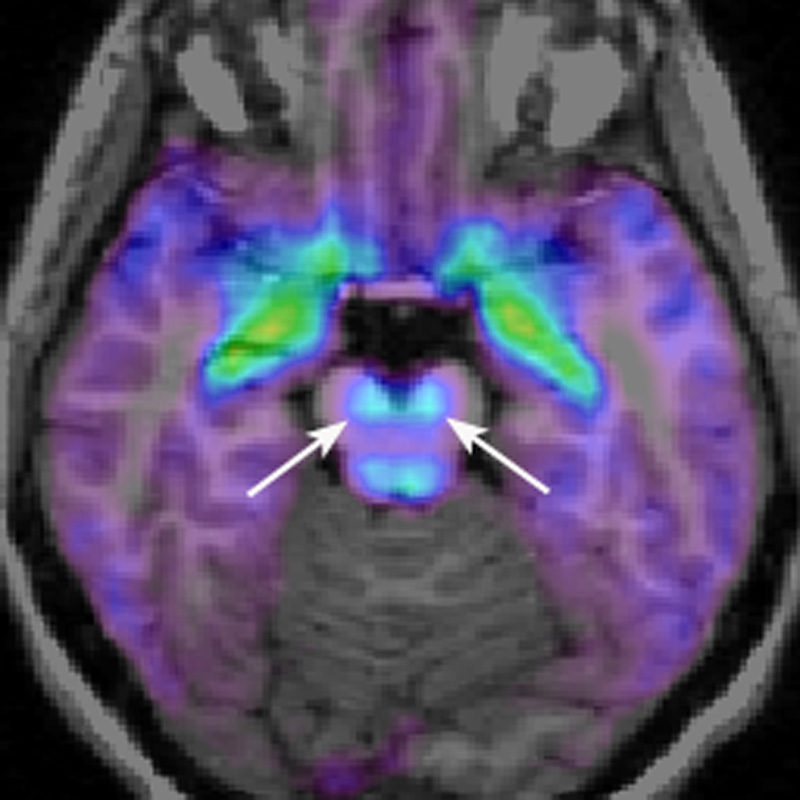

Le frecce indicano la 'substantia nigra'.

Partendo dal presupposto infatti che tremori, impossibilità ad eseguire movimenti validi, come il deambulare, ad esempio, sono dovuti alla distruzione cellulare a livello cerebrale in quella che si chiama ” substantia nigra “, si sarebbe osservato che tali cellule non periscono a causa della dopamina e dei canali del calcio, compresa l’alfa-sinucleina, ma tale morte cellulare avverrebbe per via del fatto che questi tre fattori, unendosi fra di essi, determinano la morte cellulare.